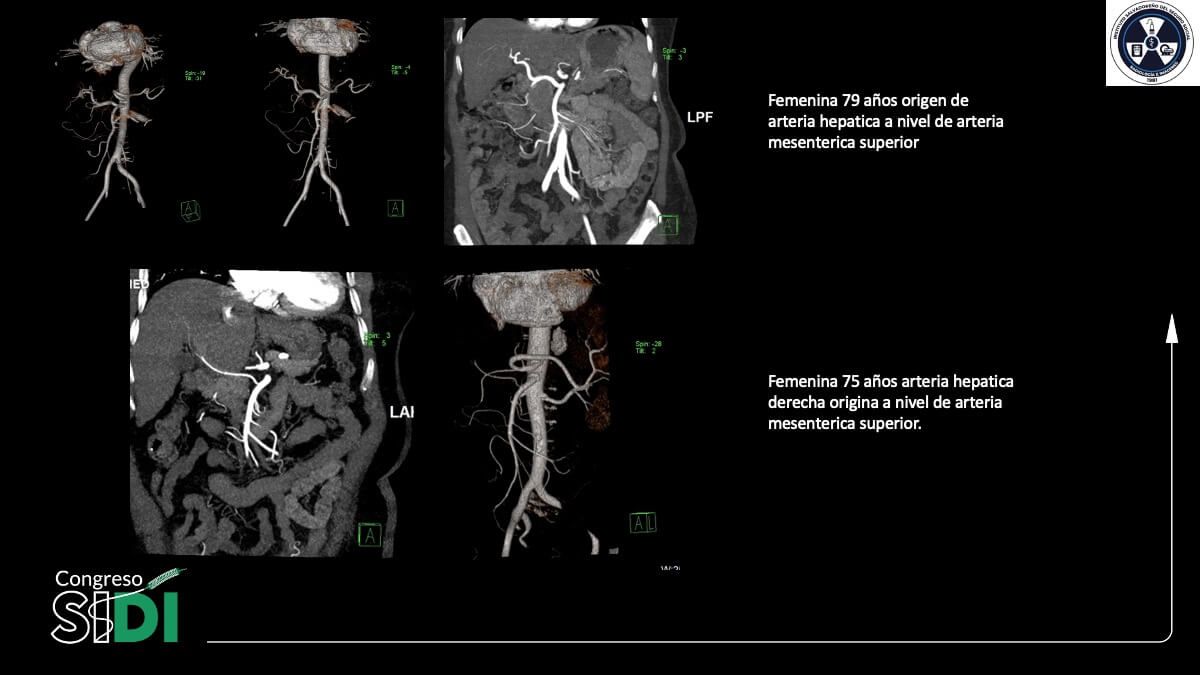

TACE en hepatocarcinoma con variaciones anatómicas arteriales: reporte de casos

Dr. David Alonso Melara